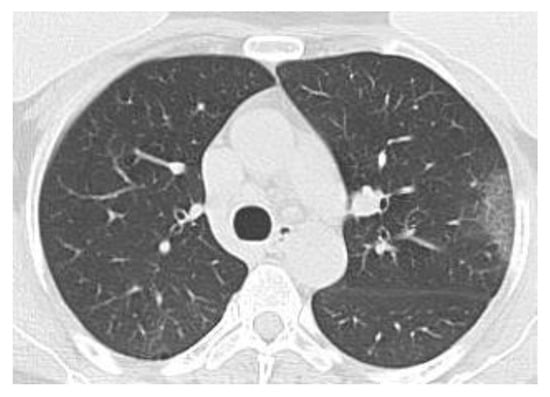

CT Lung Picture Interpretation

The usual ordinary diagnostic procedure for COVID-19 is RT-PCR (reverse transcription polymerase chain reaction), which consumes a lot of time and has shallow-low sensibility. On the other hand, chest X-ray radiography (CXR) is the primal imagistic modality that is utilized, as it is easily disposable and assures immediate good results. Nevertheless, it is well-known to have reduced sensibility in comparison to CT (computed tomography), which can be utilized efficiently in connection with other diagnosis procedures [18]. So, CT has been recognized as a clinically significant board for the correct diagnosis and disease understanding of subjects with COVID-19. Various medical studies have confronted the CT pictures of contaminated patients with certified COVID-19 clinical confirmation, with a specificity of 37% and a sensitivity of 94% [19,20].

Figure 8 shows the complete module of some lung CT images affected by COVID-19 and images of lungs that did not suffer from COVID-19, unaffected by the virus, practically healthy lungs.

We mention that the set of images from Figure 8 and the license to use them can be found online at the address indicated in the bibliographic reference [21].